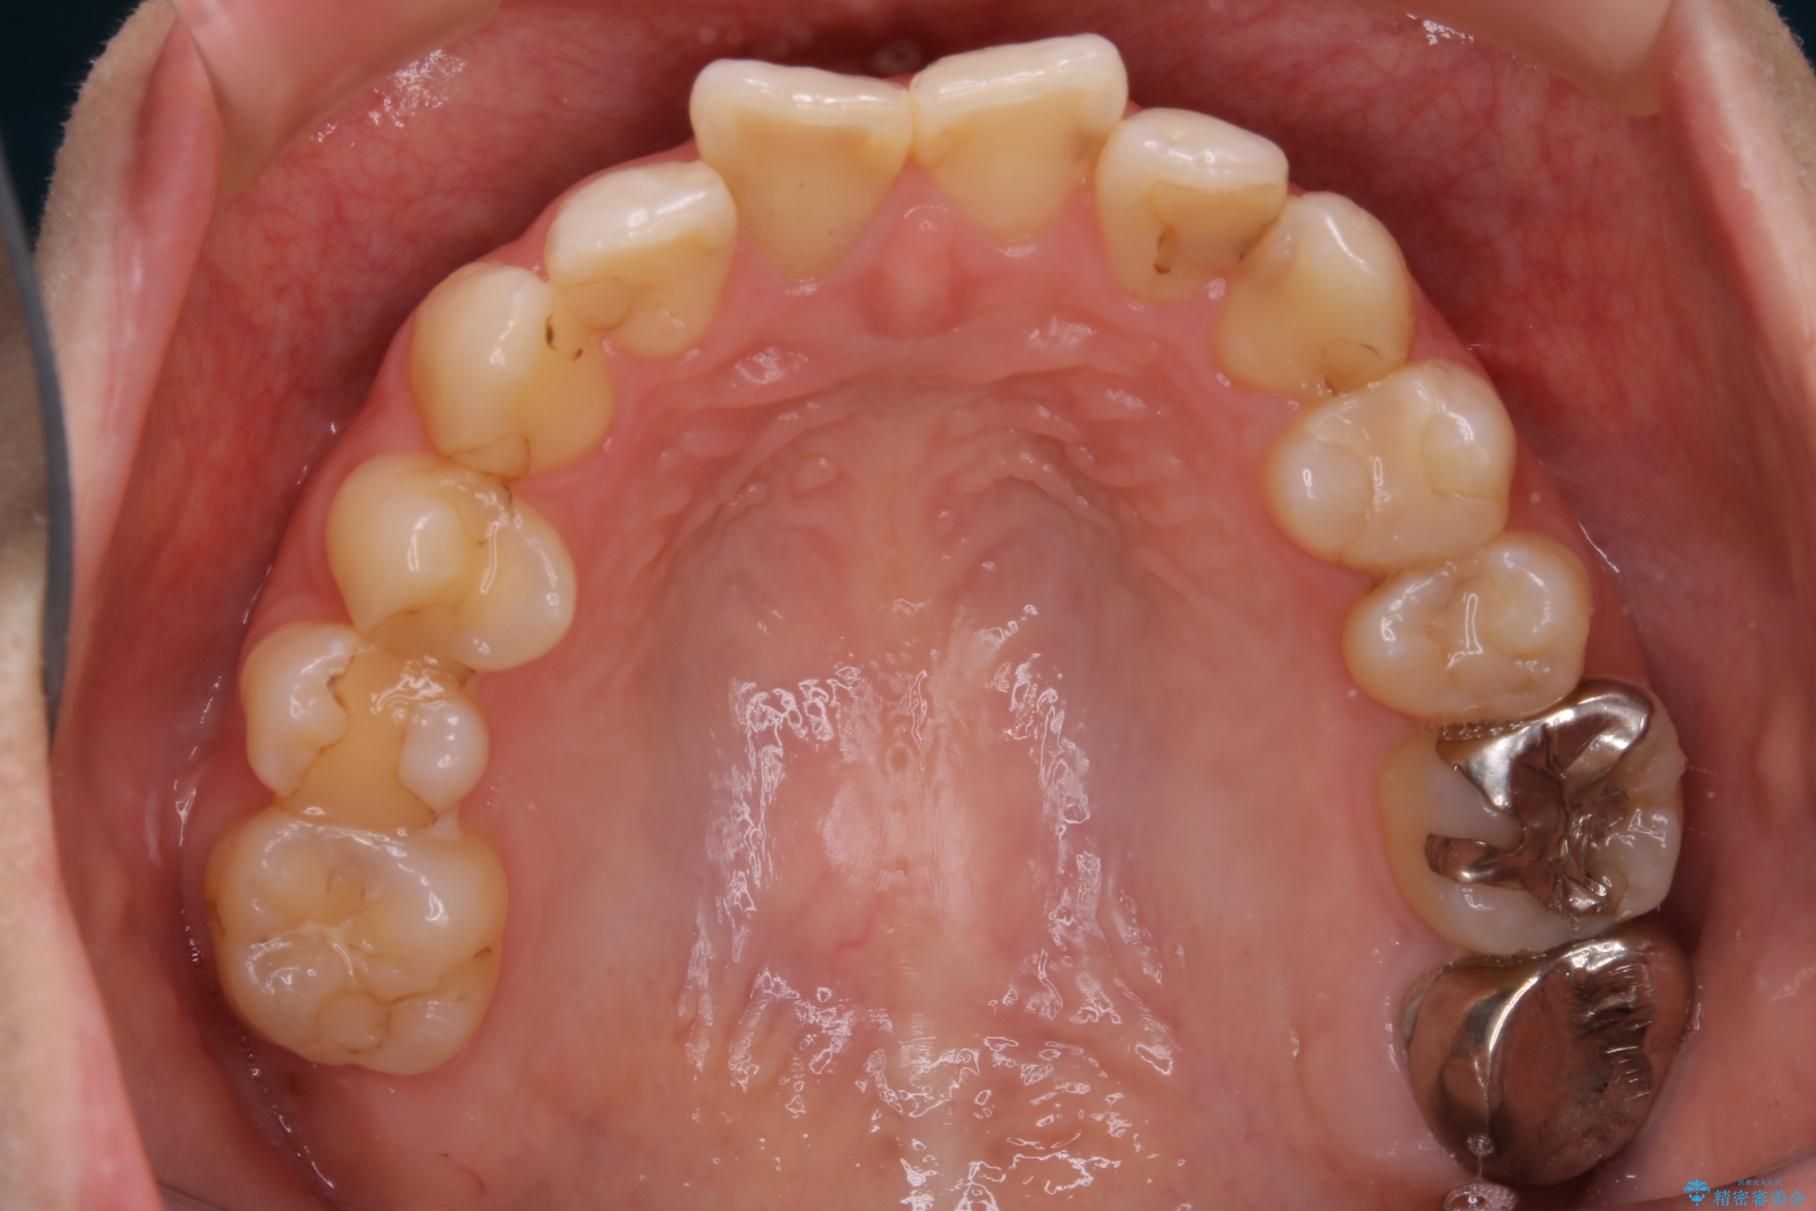

20代 女性 非抜歯で歯列をコンパクトに

前歯のガタつき、噛み合わせの不調を改善したいとご来院されました。

目立たない装置で矯正したいと希望されたため、インビザライン(マウスピース矯正)による非抜歯矯正を行いました。矯正を始める前に、虫歯などがあれば、先にすべて治療して全体のお口の状態を整えます。

治療前